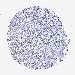

CANCER BREAST CANCER Show tissue menu

BRCA TCGA BRCA VALIDATION PROTEIN EXPRESSION

ANTIBODIES

AND

VALIDATION